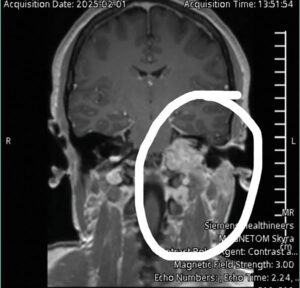

After a CT scan and MRI, I learned that I had a mass on my brain and could not go home. The nurse kneeled beside me and told me it looked cancerous and aggressive.

I had three angiograms to shrink the tumor and cut off its blood supply before brain surgery. I recently had another surgery to get the filters that prevent blood clots from traveling to my heart and lungs removed. I am doing so much better!